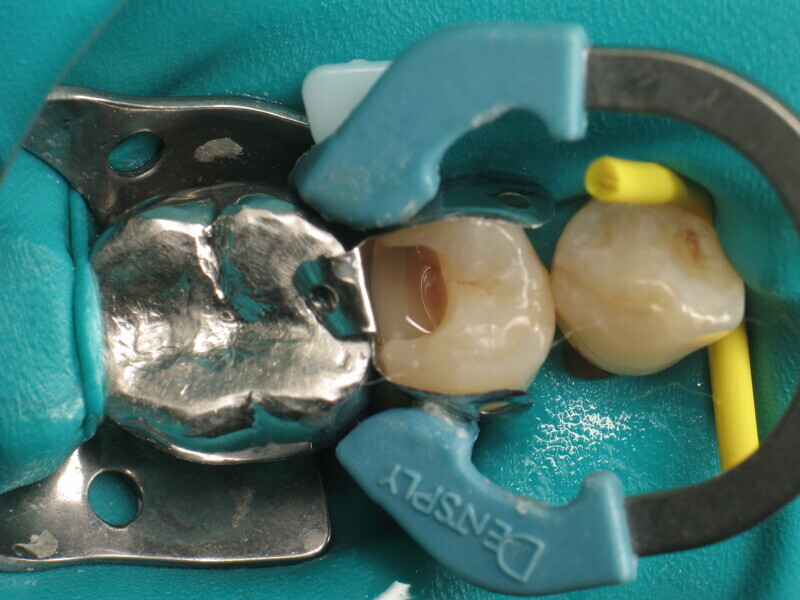

Le cas clinique décrit dans cet article porte sur une cavité de classe II sur une prémolaire (45) qui sera restaurée à l’aide d’un composite thermovisqueux (Fig. 1). La dent est isolée avec une digue en latex (Fig. 2). La cavité de classe II est ensuite nettoyée (Fig. 3). Afin d’obtenir une paroi distale anatomiquement correcte, une matrice, un coin et un anneau sont placés (Fig. 4). L’émail dentaire est ensuite mordancé pendant 30 secondes et la dentine pendant 15 secondes (Conditioner 36, Dentsply Sirona ; Fig. 5) puis rincé abondamment (Fig. 6). En raison de la faible épaisseur de dentine restante, une protection pulpaire (Telio Desensitizer, Ivoclar) est également appliquée (Fig. 7). L’adhésif (Futurabond DC, VOCO) est déposé dans la cavité pendant 20 secondes puis séché 5 secondes sous un jet d’air non gras et enfin, photopolymérisé pendant 10 secondes (Figs. 8 et 9). Pour un mouillage optimal, le fond de la cavité est recouvert d’un composite fluide extrêmement fin (GrandioSO Light Flow, A3.5, VOCO) et durci en 20 secondes (Figs. 10 et 11).